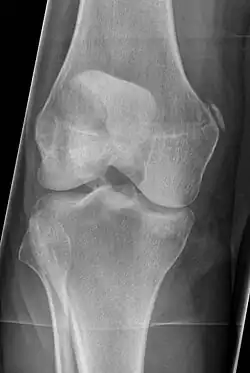

Pellegrini-Stieda syndrome. Also visible is a fracture of the patella.